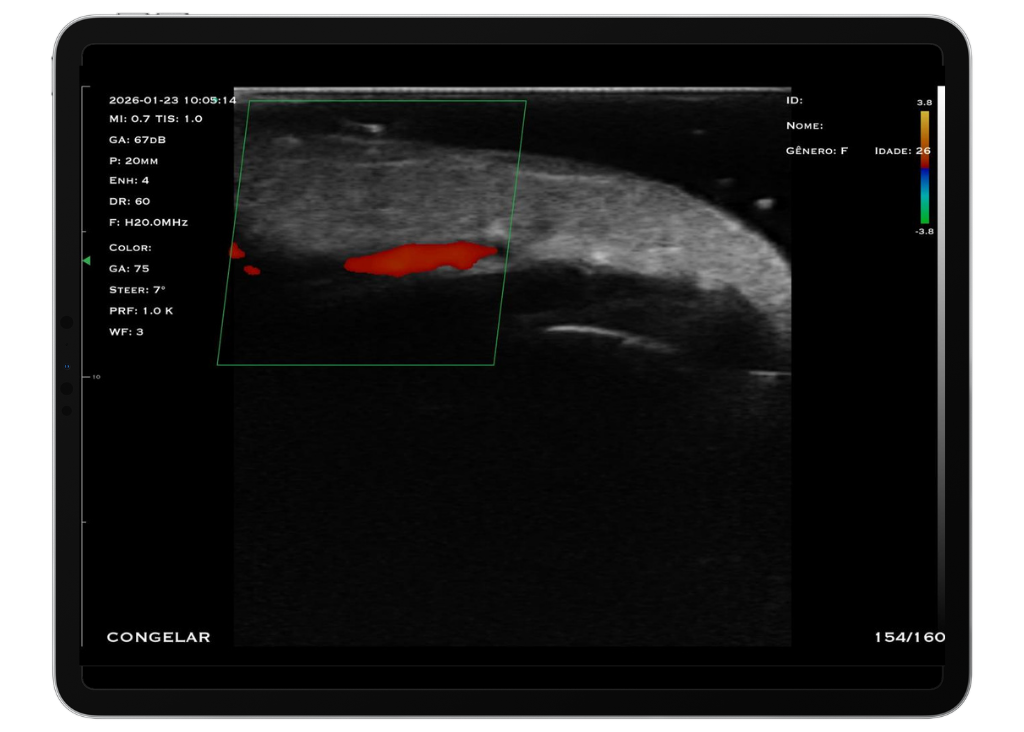

Com tecnologia linear de alta frequência (10 a 14 MHz), o modelo M4D é a escolha ideal para quem busca alta resolução em exames superficiais, com foco em detalhamento e precisão.

O trasdutor linear oferece imagens nítidas e detalhadas, permitindo a visualização precisa de estruturas como pele, tecido subcutâneo, músculos, tendões e articulações. A alta frequência garante excelente resolução para exames que exigem detalhamento extremo.

Frequência: Linear (16 – 20 MHz)

Profundidade: Até 4 cm

Modos: B, B/M, Color, PDI e PW

Aplicações: Visualização de articulações periféricas, avaliação de estruturas faciais, preenchedores, acesso PICC, acessos superficiais, anestesia pediátrica e bloqueios periféricos.